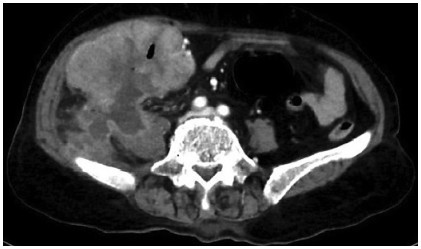

Abstract: Mixed neuroendocrine nonneuroendocrine neoplasms (MiNENs) are rare neoplasms of the gastrointestinal tract, where the neuroendocrine as well as the nonneuroendocrine components each comprise at least 30% of the tumor. Of all cases of colorectal malignancies, MiNENs constitute around 3–9.6%, with only a few cases reported to be arising in the cecum. Since majority present with nonspecific clinical and radiological findings, its diagnosis preoperatively is almost impossible and these are usually diagnosed after histopathological examination of the resected specimen. Owing to the rarity of these tumors as well as lack of complete molecular characterization, optimal treatment remains unestablished. We, here, report a rare case of MiNENs of the cecum infiltrating the right psoas muscle and presenting with perforation for which right hemicolectomy and en bloc excision of the involved psoas muscle was done followed by adjuvant chemotherapy.